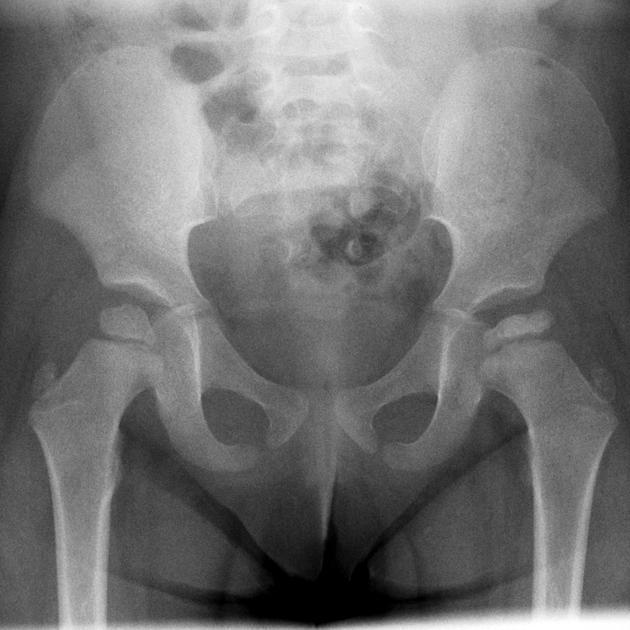

7M. Diagnosis?

Legg-Calvé-Perthes disease - an idiopathic avascular necrosis (AVN) of the growing femoral epiphysis seen in children.